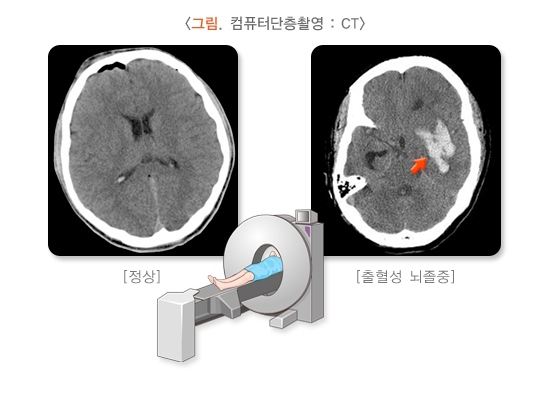

1) 컴퓨터단층촬영

뇌 컴퓨터단층촬영(Computed Tomography, CT)은 안전하고 빠르며, 결과를 보면 혈관이 막혀서 생긴 문제인지(허혈성), 터져서 생긴 문제인지(출혈성) 쉽게 구분할 수 있습니다. 일과성 허혈 발작이 의심될 때 즉시 시행하면 뇌출혈이나 종양 등 뇌 병변을 구분하거나 치료 방침을 정하는 데 큰 도움이 됩니다. 사진에서 뇌 경색 부위는 검게 보이며 뇌출혈은 희게 보입니다. 그러나 일과성 허혈 발작은 CT상 대부분 정상으로 보이므로 검사 결과가 정상이라고 해서 안심해서는 안 되며, 의사와 상의해 추가 검사 및 처치를 받아야 합니다.